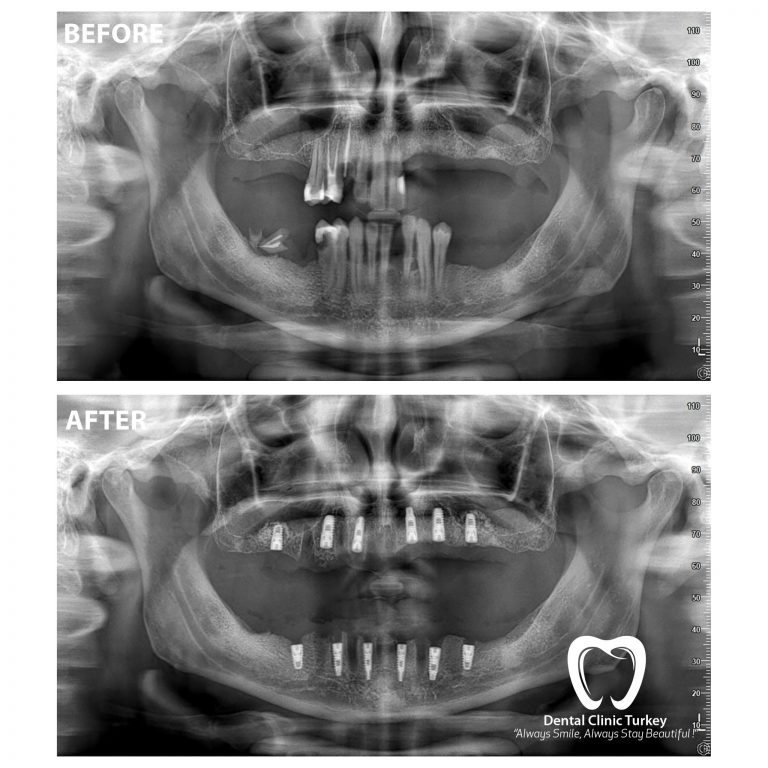

From www.turkeydentalclinic.com

What is Panoramic XRay? Antalya Dentist, Turkey Dental Clinic Dental Panoramic X Ray Cpt Code  The picture shows all the. The d0220 dental code, officially recognized by the american dental association (ada), refers to the procedure for. Code on dental procedures and nomenclature effective january 1, 2022 d0367 cone beam ct capture and interpretation with field of view of. This guide is published to educate dentists and others in the dental community on selection and. Dental Panoramic X Ray Cpt Code.